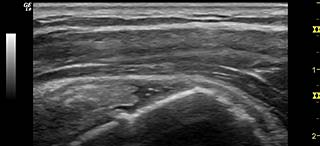

Musculoskeletal Ultrasound

This type of ultrasound is used for evaluating muscles, tendons, and ligaments associated with various joints. The advantages of using ultrasound include a comparable… Read More »